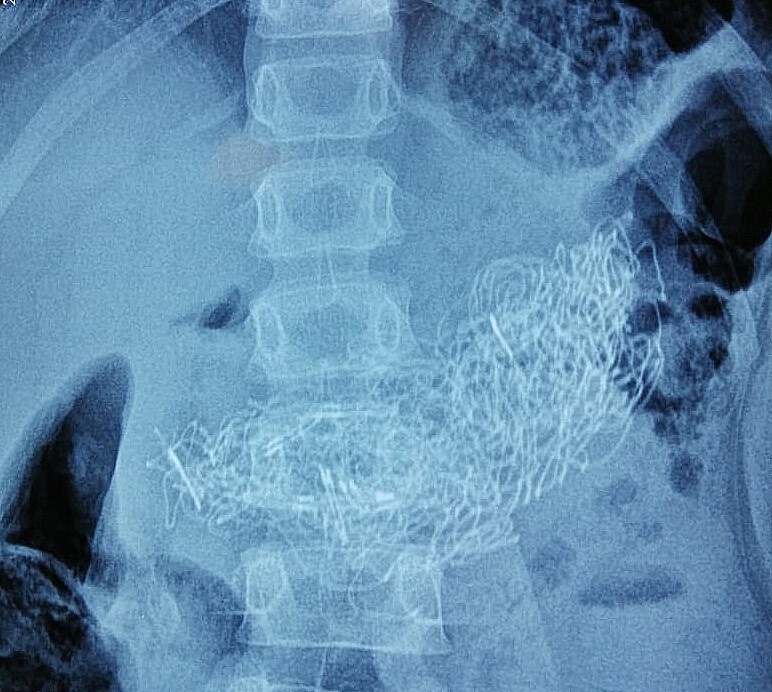

Необычные находки: инородные тела на рентгенограмме брюшной полости